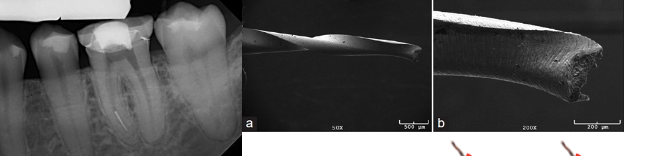

cylic fatigue

freely rotating in a curvature

generation of tension/compression cycles

cyclic fatiugue = failure

torsional fatigue

bind to dentinal wall

rotate but not bond portion